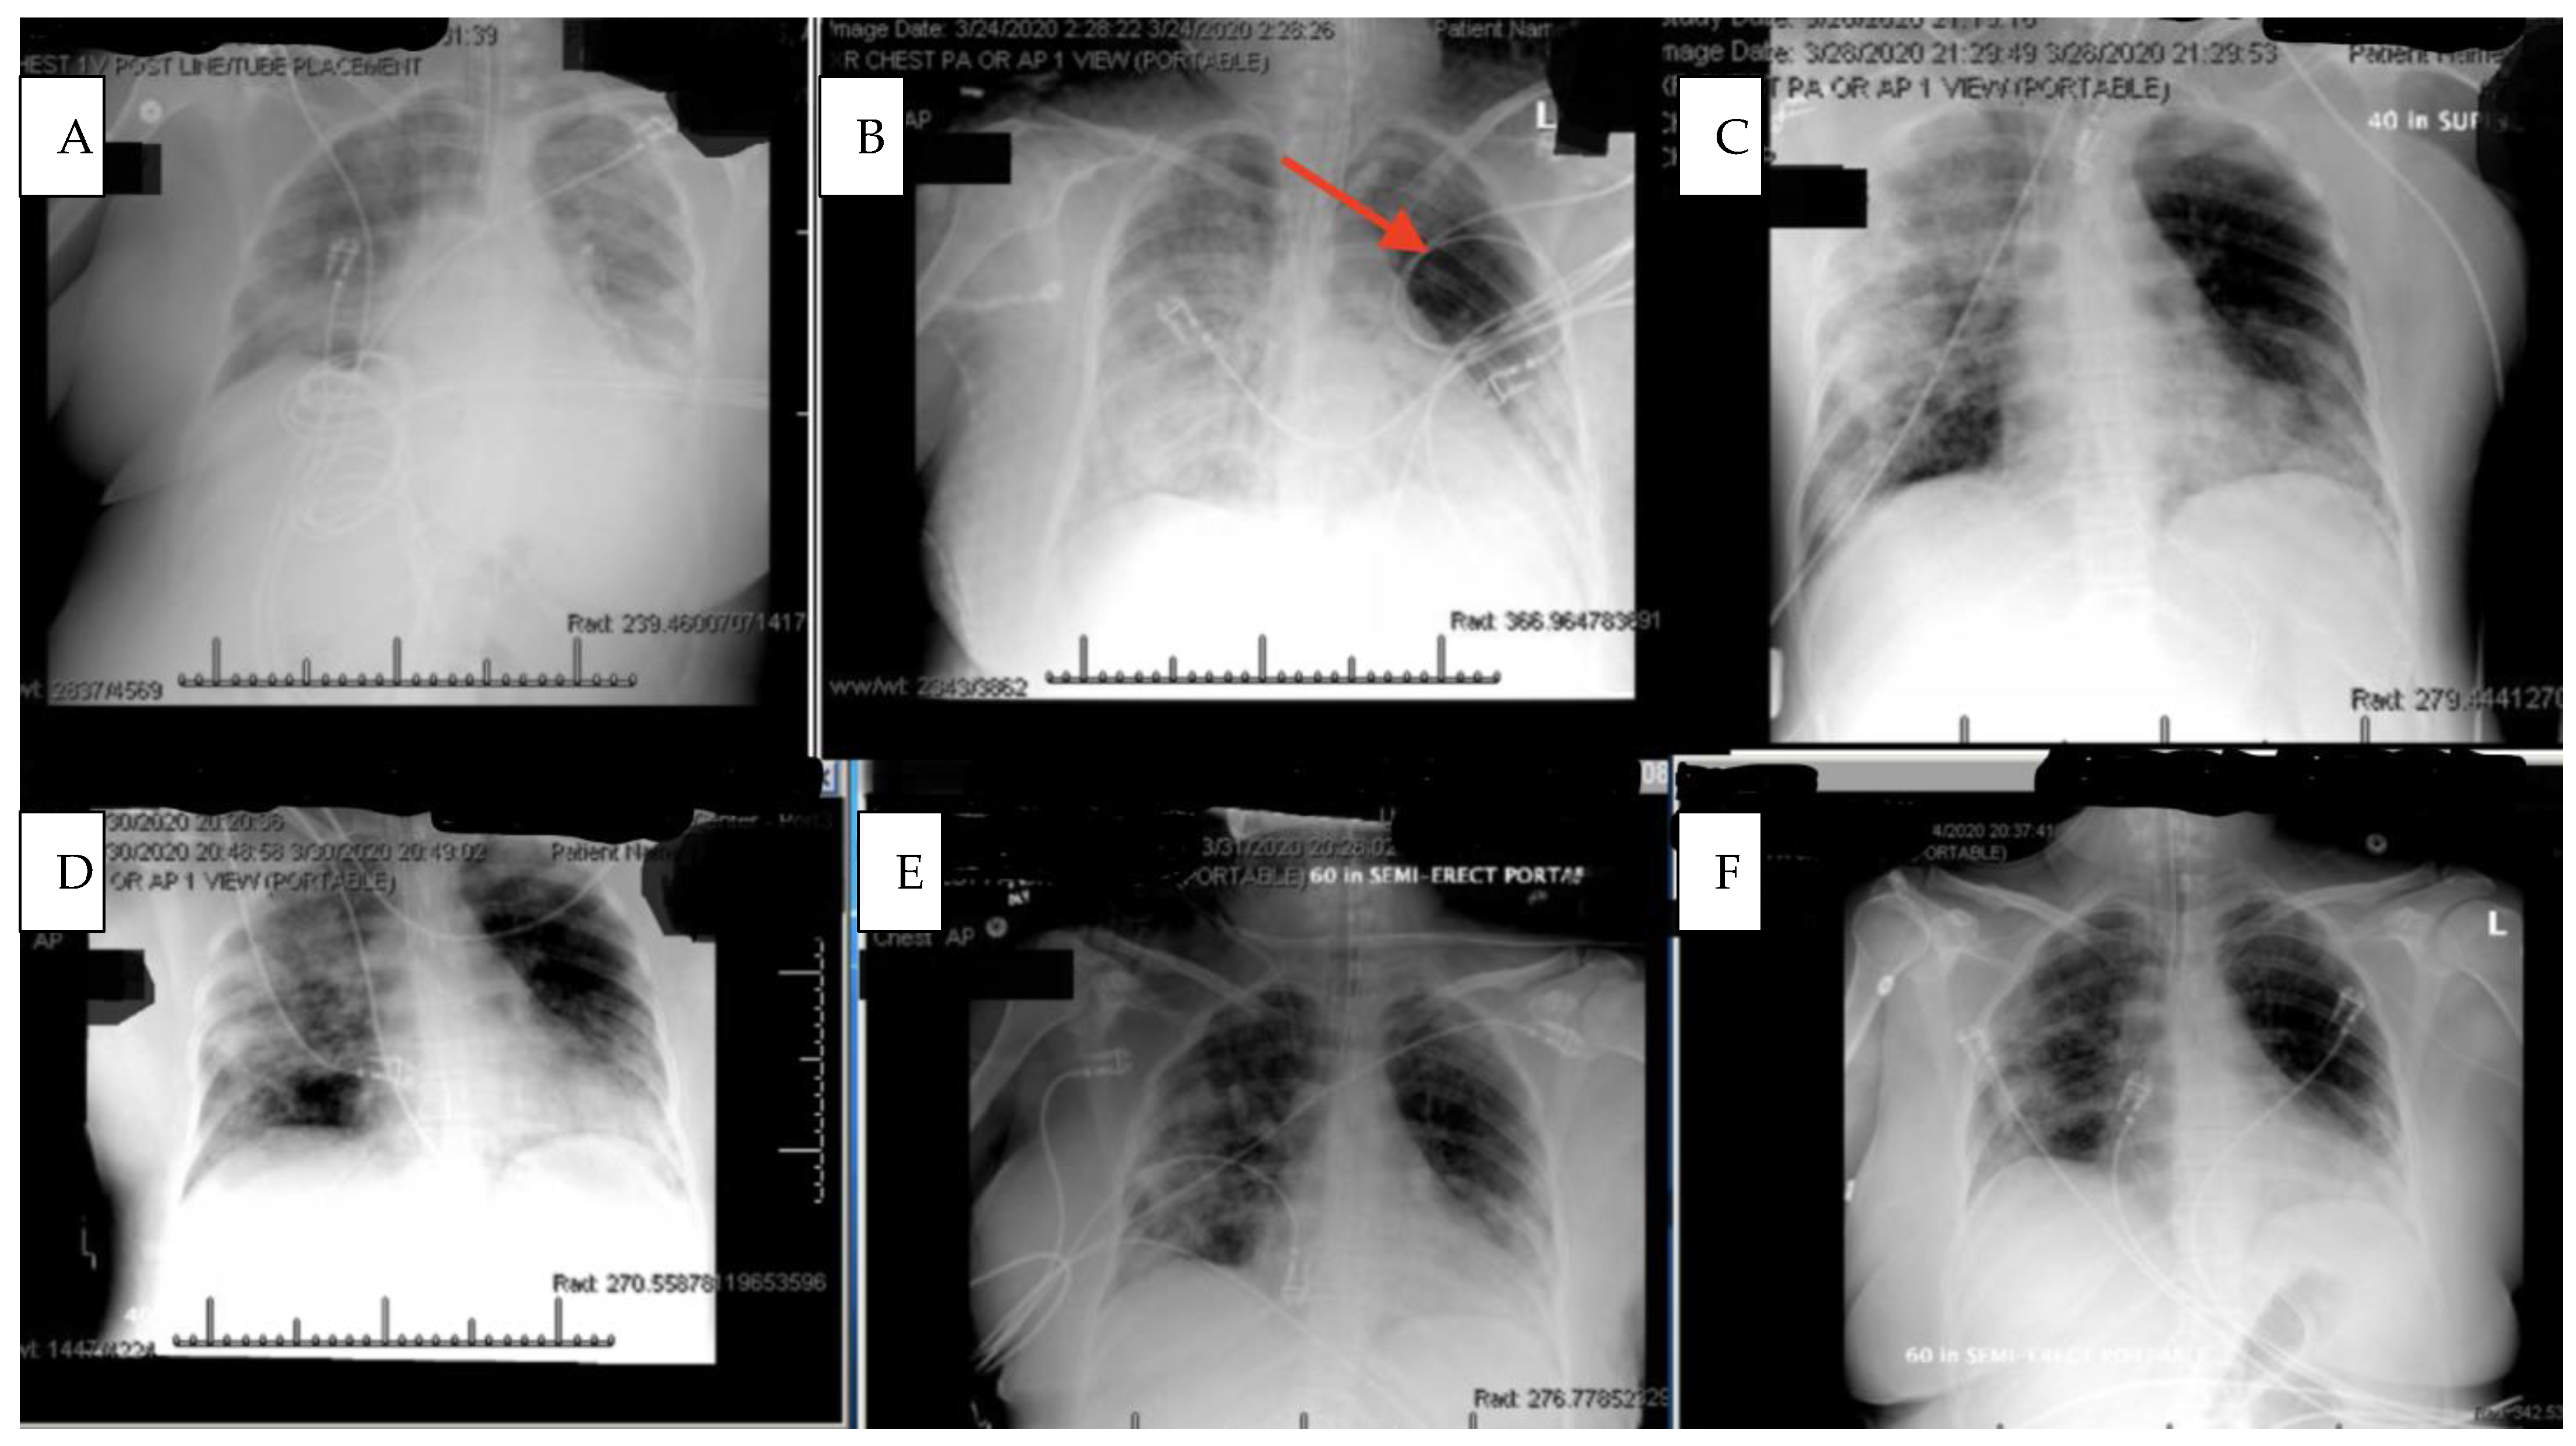

Within 4 h after the first dose of eculizumab, her chest X-ray improved, Figure 2, and her Murray score improved from 13 to 10. She had a daily improvement in Murray score except on 27 March 2020 when her endotracheal tube moved out of place while she was prone and had to be readjusted, in which case her Murray score rose slightly but still remained lower than her pretrial baseline. Another 900 mg IV eculizumab dose was given 4 days after the first dose and, again, her chest X-ray improved. Her hydroxychloroquine was stopped by the infectious disease team on 28 March 2020 due to a possible contribution to a normocytic anemia. Norepinephrine was discontinued on 29 March 2020 as her blood pressure stabilized. The patient was able to be adequately oxygenated in the supine position and her rotabed was discontinued on 31 March 2020. On 2 April 2020, the patient’s third dose of eculizumab 900 mg IV was given and her Murray score improved from 8/16 on 1 April 2020 to 6/16 recorded seven hours after the third dose of eculizumab was given on 2 April 2020 Figure 3. On 3 April 2020 the medical critical care team started to wean the patient’s sedation (propofol, fentanyl, and midazolam). The patient passed a spontaneous breathing trial and followed appendicular commands on 4 April 2020. Mechanical ventilation was continued to allow the sedation to fully wear off in preparation for extubation. The patient’s Murray score had decreased to 3/16, she was able to oxygenate in the supine position, remained afebrile, and did not require presser medications. She was successfully extubated on 5 April 2020, Figure 3. She had amnesia and some bradyphrenia but was otherwise neurologically normal and even “face-timed” on the phone with family a few hours subsequent to extubation. Arm swelling and pain was noted and an upper extremity DVT was discovered. The patient completed a course of inpatient rehabilitation and was discharged home. She completes all ADLs and IADLs on her own.

It is also critical to point out that the patient was intubated and almost died while on hydroxychloroquine chronically and did not clinically improve with the concomitant administration of azithromycin. It was not until eculizumab was delivered that the patient began to improve, Figure 2. The patient also continued to improve despite hydroxychloroquine being stopped by the infectious disease consultant due to a concern for anemia. Her upper extremity DVT may have been provoked from indwelling lines and immobility over several weeks on mechanical ventilation. Complement inhibition typically works against complement induced prothrombotic states. COVID-19 is known to provoke DVTs, pulmonary emboli, strokes, and a general tendency towards a prothrombotic state in many patients.

Figure 2. Chest X rays prior to and during eculizumab therapy. (A): Chest X ray taken 22 h prior to first dose of eculizumab deonstrates bilateral extensive pulmonary infiltration consistent with Covid-19 related Adult Respiratory Distress Syndrome. (B): four hours after the first eculizumab dose (red arrow denotes area of improved aeration). (C): Following the second dose of eculizumab. (D): Following the third dose of eculizumab. (E): Following the fourth dose of eculizumab. (F): Extubation.